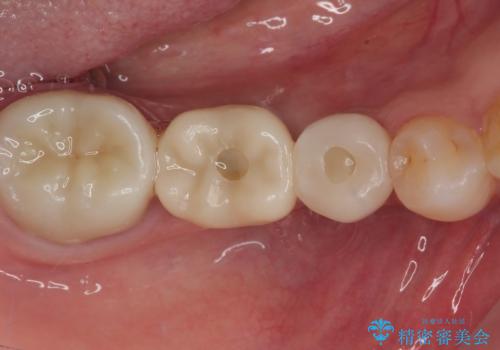

インプラント治療をきっかけに、銀歯を全てセラミックに替えていきました。

人の目を気にせずに、大きく口を開けて笑えるようになりました。